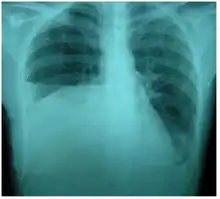

| Right sided pleural effusion caused by urinothorax | |